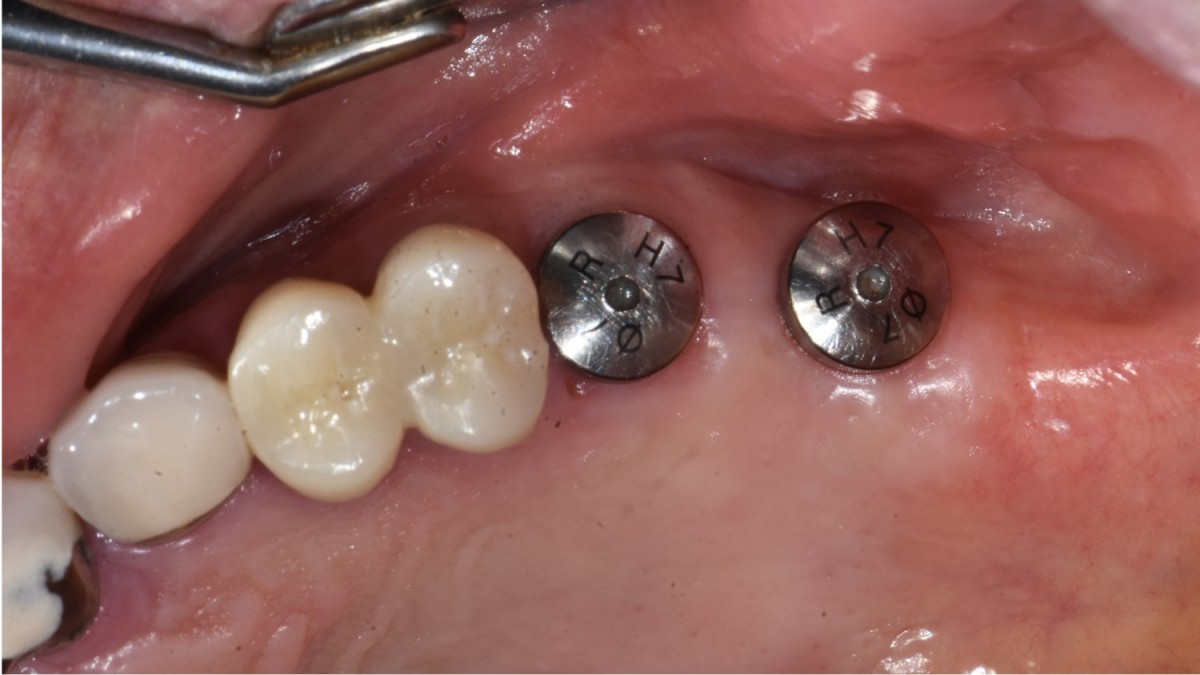

▲2 implants were placed. ArumDentistry NB1 5*10 (30Ncm) in the 1st molar and 5*10 (10Ncm) in the 2nd molar.